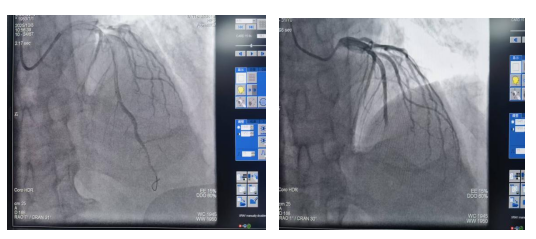

导管室内,气氛紧张而有序。手术团队已做好一切准备,严阵以待。冠脉造影结果很快证实了之前的判断:患者心脏冠状动脉前降支中段完全闭塞,这是急性心肌梗死中最为凶险的“急性前壁心肌梗死”类型,心肌细胞正处于缺血性坏死的边缘,每一分每一秒都至关重要。

考虑到患者病情危重,高新院区紧急联系并请求东院区心内科李晓妹副主任火速驰援。最终,在李晓妹副主任和李杨医师的精准操作下,为患者紧急施行“经皮冠状动脉造影术+经皮冠状动脉腔内成形术(PTCA)+血栓抽吸术”。手术团队凭借精湛的技术和稳定的手技,精准操作导管,成功抽吸出大量新鲜血栓,并随即使用球囊对闭塞血管进行扩张。随着球囊的扩张和血流的恢复灌注,患者原本堵塞的血管瞬间“打通”,术中患者即感胸痛症状明显缓解,生命体征逐渐平稳。整个手术过程紧张而高效,为患者成功“抢”回了濒死的心肌。